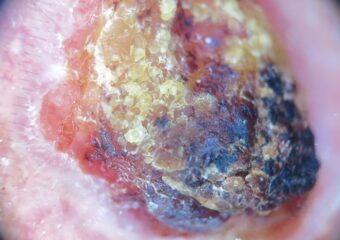

Melanoma Case Study

Not a “Boil” but an Advanced Melanoma

Deborah S. Sarnoff, MD

The power of denial can be strong. This man believed the large, dark growth on his back was a boil, despite oozing and bleeding for months. He kept bandaging it and thought it was just slow to heal. When he was finally referred to Dr. Sarnoff, a biopsy and other tests revealed a melanoma so large and deep that it had already spread to the man’s liver and brain. He was referred to an oncologist and began an immunotherapy regimen that did not appear to be working, which happens with some patients. (Thanks to recent innovations, there may be other treatment options, including participation in a clinical trial.) This is a powerful reminder of the importance of early detection.